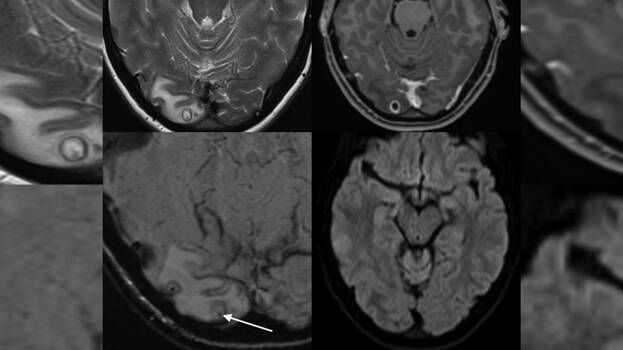

അടുത്തിടെ കഠിനമായ തലവേദന ഒരാഴ്ചയിലേറെ നീണ്ടു നിന്നു. ഒപ്പം കാഴ്ച മങ്ങുന്നതുൾപ്പെടെയുള്ള ലക്ഷണങ്ങളും പ്രകടമായി. ഉടൻ തന്നെ യുവതിയെ ആശുപത്രിയിൽ പ്രവേശിപ്പിച്ചു. ഡോക്ടർമാർ യുവതിയെ എം.ആർ.ഐ സ്കാന് വിധേയമാക്കി. തലച്ചോറിലെ ട്യൂമറാണ് യുവതിയ്ക്ക് തലവേദനയുണ്ടാകാൻ കാരണമെന്ന് സ്കാൻ റിപ്പോർട്ടിൽ നിന്നും ഡോക്ടർമാർ നിഗമനത്തിലെത്തി. തലയിലെ മുഴ നീക്കം ചെയ്യാനായി ഡോക്ടർമാർ ശസ്ത്രക്രിയ ആരംഭിച്ചു. എന്നാൽ മുഴയ്ക്കുള്ളിൽ ഡോക്ടർമാർ കണ്ടത് ഞെട്ടിക്കുന്ന കാഴ്ചയായിരുന്നു.

ടേപ്പ് വേം (Tapeworm ) അഥവാ നാടവിരകളുടെ ലാർവകളായിരുന്നു അതിനുള്ളിൽ. ഏതായാലും ഡോക്ടർമാർ ശസ്ത്രക്രിയ വിജയകരമായി പൂർത്തിയാക്കി. യുവതി സുഖം പ്രാപിച്ചു വരുന്നു. ന്യൂറോസിസ്റ്റിസർകോസിസ് (Neurocysticercosis ) എന്നാണ് ഈ അവസ്ഥ അറിയപ്പെടുന്നത്. ടേനിയ സോളിയം ( Taenia solium) എന്നറിയപ്പെടുന്ന നാടവിരകളോ അവയുടെ മുട്ടയോ ശരീരത്തിലെത്തുന്നത് വഴിയാണ് ഇവ ഉണ്ടാകുന്നത്.